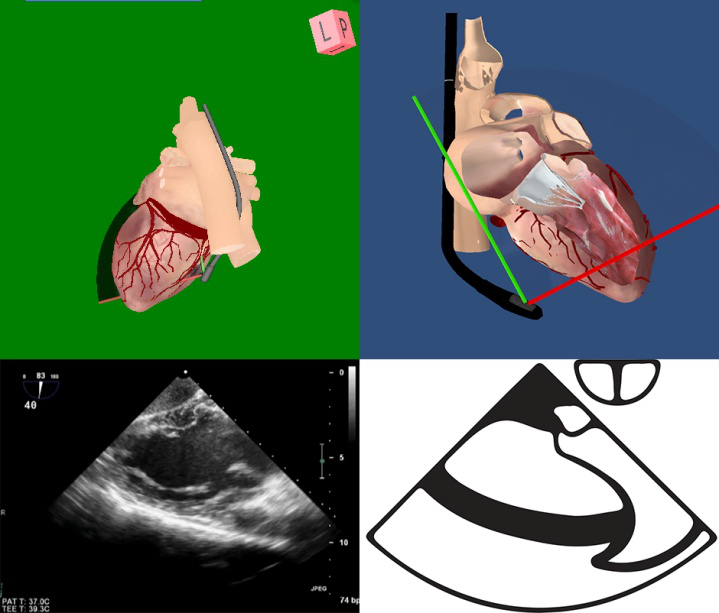

TEE切面可用来评估二尖瓣系统的每一部分,检查时将探头送至食管中段,操纵探头调整成像的角度使声平面对准二尖瓣环中心,探头晶片置于0~10度食管中段4腔心切面后开始旋转声平面,依次获得食管中段二尖瓣交界切面、食管中段左心室2腔切面、食管中段左心室长轴切面,在各个标准切面上可以观察不同小叶的功能状态,各个小叶与标准切面的对应关系如下图所示。

图10 TEE评价二尖瓣形态和功能的基本切面(标注二尖瓣分区)

TEE切面与二尖瓣分区的对应关系可用于二尖瓣脱垂部位的判断,但要注意的是:一定要将2D或3D图像与二尖瓣模型对应起来,不理解切面和模型之间的空间关系,直接用文献上的分区对应实际的超声图像会导致定位不准和交流障碍(图11,12,13,14);另外,经胃底基底段短轴切面对诊断瓣叶裂和穿孔很有帮助,彩色多普勒可以提供有关反流束起源的信息(图14)。

图11四腔心切面显示二尖瓣后叶P2区脱垂